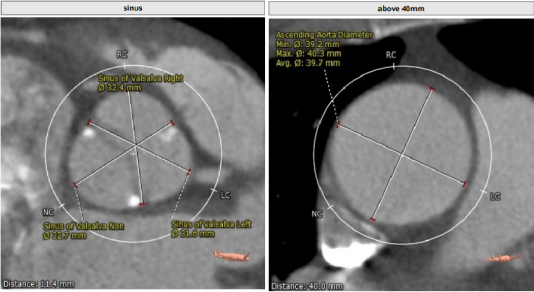

CT分析

Annulus:23.5,初选26/29瓣膜。LVOT短径19.3mm,STJ高度足够,宽度适中。

窦部空间足够,升主增宽,左右冠高度合适。

心脏角度不大,轻度钙化,左右窦黏粘;释放体位LAO 9、CRA 1;运用cusp-overlap技术定位角度;RAO17°、CAU 28° 。